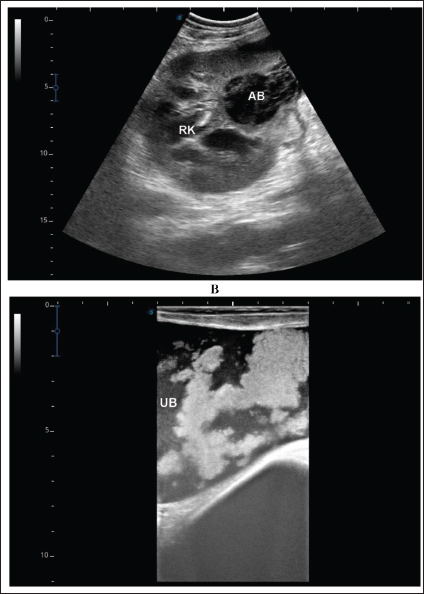

Fig. 6. Ultrasonographic findings in camel number 6. The lesion in image A appeared within the right kidney (RK). The contents are heterogenous, and the capsule is not evident. Image B shows the urinary bladder (UB) in the same animal with echogenic deposits that appeared highly echogenic compared with the echogenic urine.

A detailed description of the renal abscesses is presented in Figures 410. Figure 4 shows sonographic findings in camel number 1 with abscessation of the right and left kidneys. A large abscess measuring 12.5 × 11.6 cm with hypoechoic contents and a thick capsule was detected. A second abscess in the same camel was imaged compressing the parenchyma of the right kidney and measuring 7.2 × 7.9 cm with echogenic contents and a thick capsule. Figure 5 shows ultrasonographic results in camel numbers 2 and 4 with right kidney abscesses. The lesions in camel number 2 appeared markedly large, compressing the renal parenchyma, with echogenic contents and a thickened capsule. The lesion in camel number 4 appeared to compress the renal parenchyma of the right kidney, measuring 6.7 × 8.2 cm with echogenic contents and a thick capsule. In addition, Figure 6. clarifies sonographic findings in camel number 6, where the abscess appeared within the right kidney. The contents were heterogeneous, but the capsule could not be imaged. The urinary bladder in the same animal was imaged with echogenic deposits that appeared highly echogenic compared with the echogenic urine.